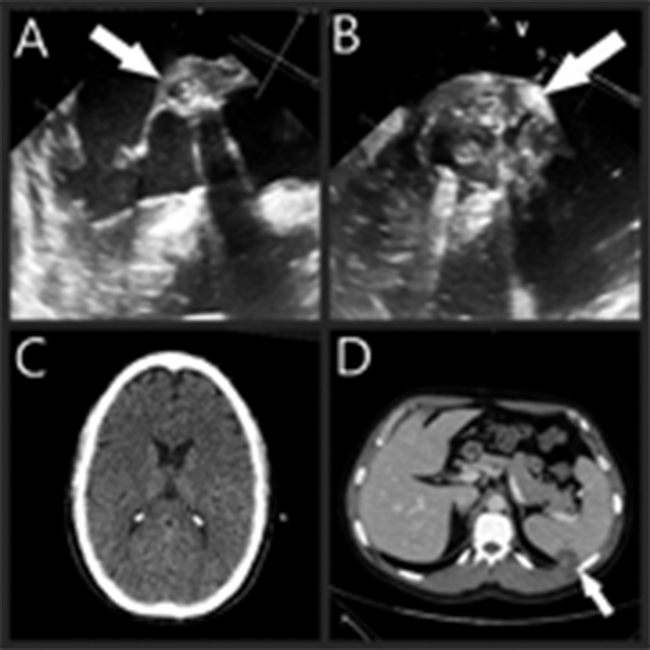

El paciente ingresó a nuestro centro con un cuadro febril persistente; en el ecocardiograma transesofágico (ETE) de ingreso se observaron imágenes compatibles con endocarditis de prótesis aórtica, con vegetación de 15 mm; a través de esa vegetación protuía un absceso perianular y el compromiso de la membrana mitroaórtica y la valva anterior de la válvula mitral (Figura 1. A, B), con aislamientos en hemocultivos en el centro de origen de bacilos Gram negativos no fermentadores; se inició una terapia empírica con piperacilina tazobactam, levofloxacina y trimetoprima sulfametoxazol.

Se realizó una Tomografía computada (TC) de cerebro sin evidencia de alteraciones anatómicas (Figura 1. C), diferente de la TC de abdomen en la cual se visualizaron imágenes compatibles con focos embólicos esplénicos (Figura 1. D).